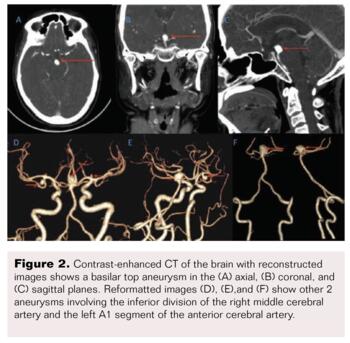

A 46-year-old woman presented with sudden onset headache associated with 2 to 3 episodes of vomiting and giddiness. On examination, her Glasgow Coma Scale (GCS) was 15/15 and power in all four limbs was 5/5. A non-contrast CT brain scan (Figure 1) revealed a diffuse SAH more predominant in the basal cisterns on the left side with intraventricular extension into the 4th ventricle (Fisher grade 4). There was no hydrocephalus. A CT angiogram (Figure 2) and diagnostic cerebral angiogram (Figure 3) demonstrated 3 intracerebral aneurysms in the following locations: inferior division of the right middle cerebral artery (MCA), 4.3 x 5 x 3.6 mm (AP x ML x CC); A1 segment of the left anterior cerebral artery (ACA), 2.1 x 2.2 x 1.4 mm; and basilar top, 11 x 8.1 x 8.3 mm with a neck measuring 6.8 mm. Based on the distribution of the SAH and morphology of the aneurysms, the basilar top aneurysm was assumed to be the cause of the SAH. Standard medical management included nimodipine, antiepileptics, antihypertensives, and analgesics.